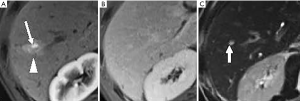

THED

THED indicate transient increased attenuation or signal intensity differences during the HAP, which return to normal or near-normal in the portal venous phase (PVP) and equilibrium phase. It typically manifests as a peripheral, wedge or cone shaped area with a straight margin, and contains normal vessels (Figure 3). THED usually occur in functional HAPS (transsinusoidal shunts and transplexal shunts) caused by decreased portal or hepatic venous flow due to contrast material passage from the high-pressure arterial blood into a low-pressure portal vein branch, thus enhancing a focal area of the liver before the adjacent parenchyma is enhanced through flow from the normal portal venous system (18,19).